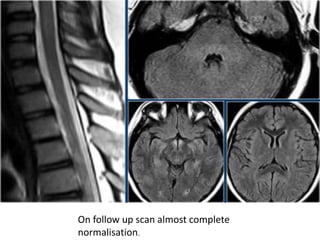

These are images of a teenage child with a typical history of respiratory tract infection

There is swelling and cord involvement and no enhancement

The imaging findings and clinical history is typical of ADEM

The follow up MR shows that the

cord has returned to normal again

Another case of ADEM.

Notice the typical involvement of the pons and basal ganglia.

On follow up scan almost complete

normalisation.